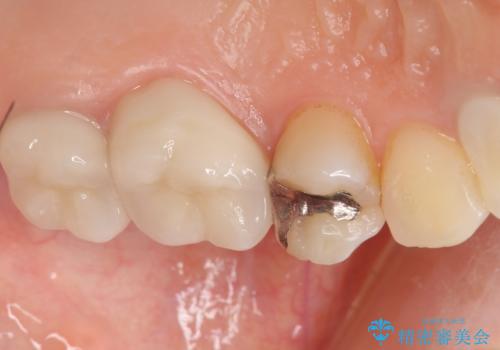

銀のつめものを除去したところ、大きなう蝕を認めました。

咬合力が強いため、割れる心配がなく強度の高いPGA(ゴールド)インレーをご希望されました。